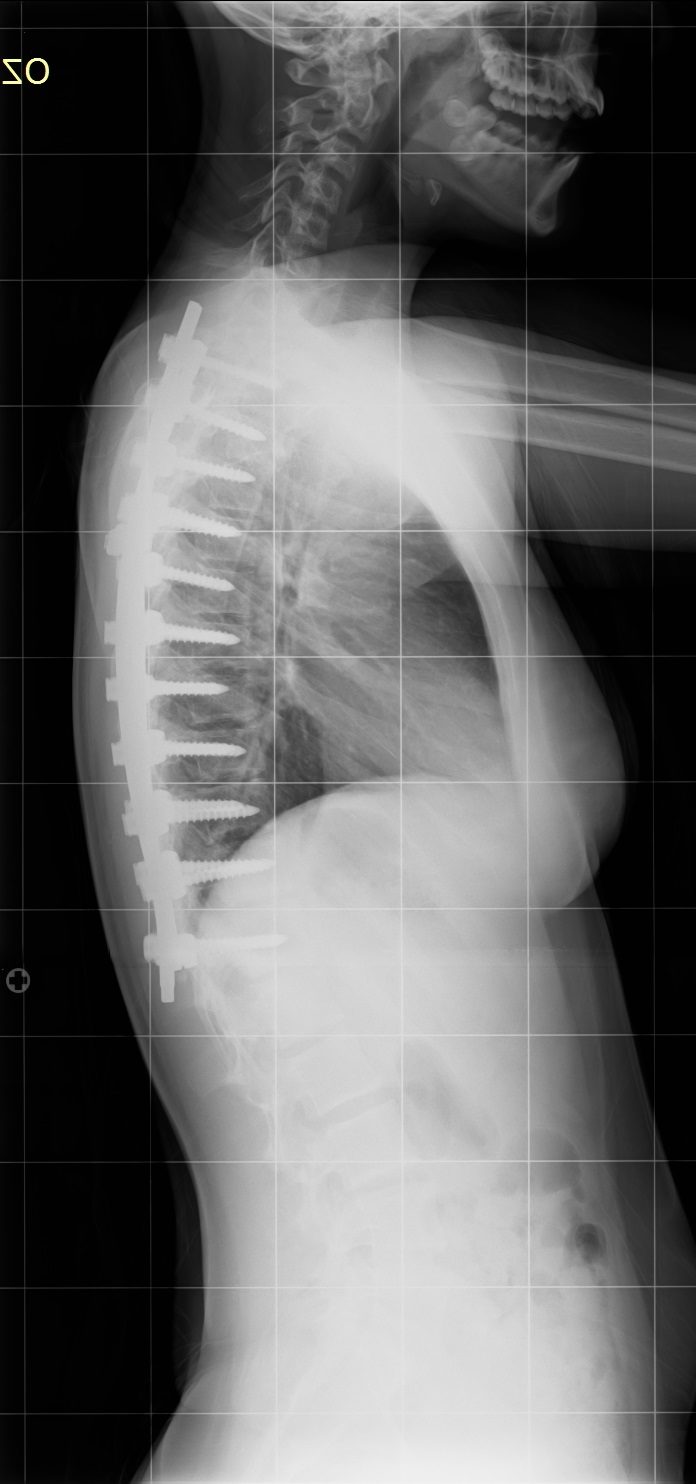

16 Yaşında Kadın Hasta

Ameliyat Sonrası